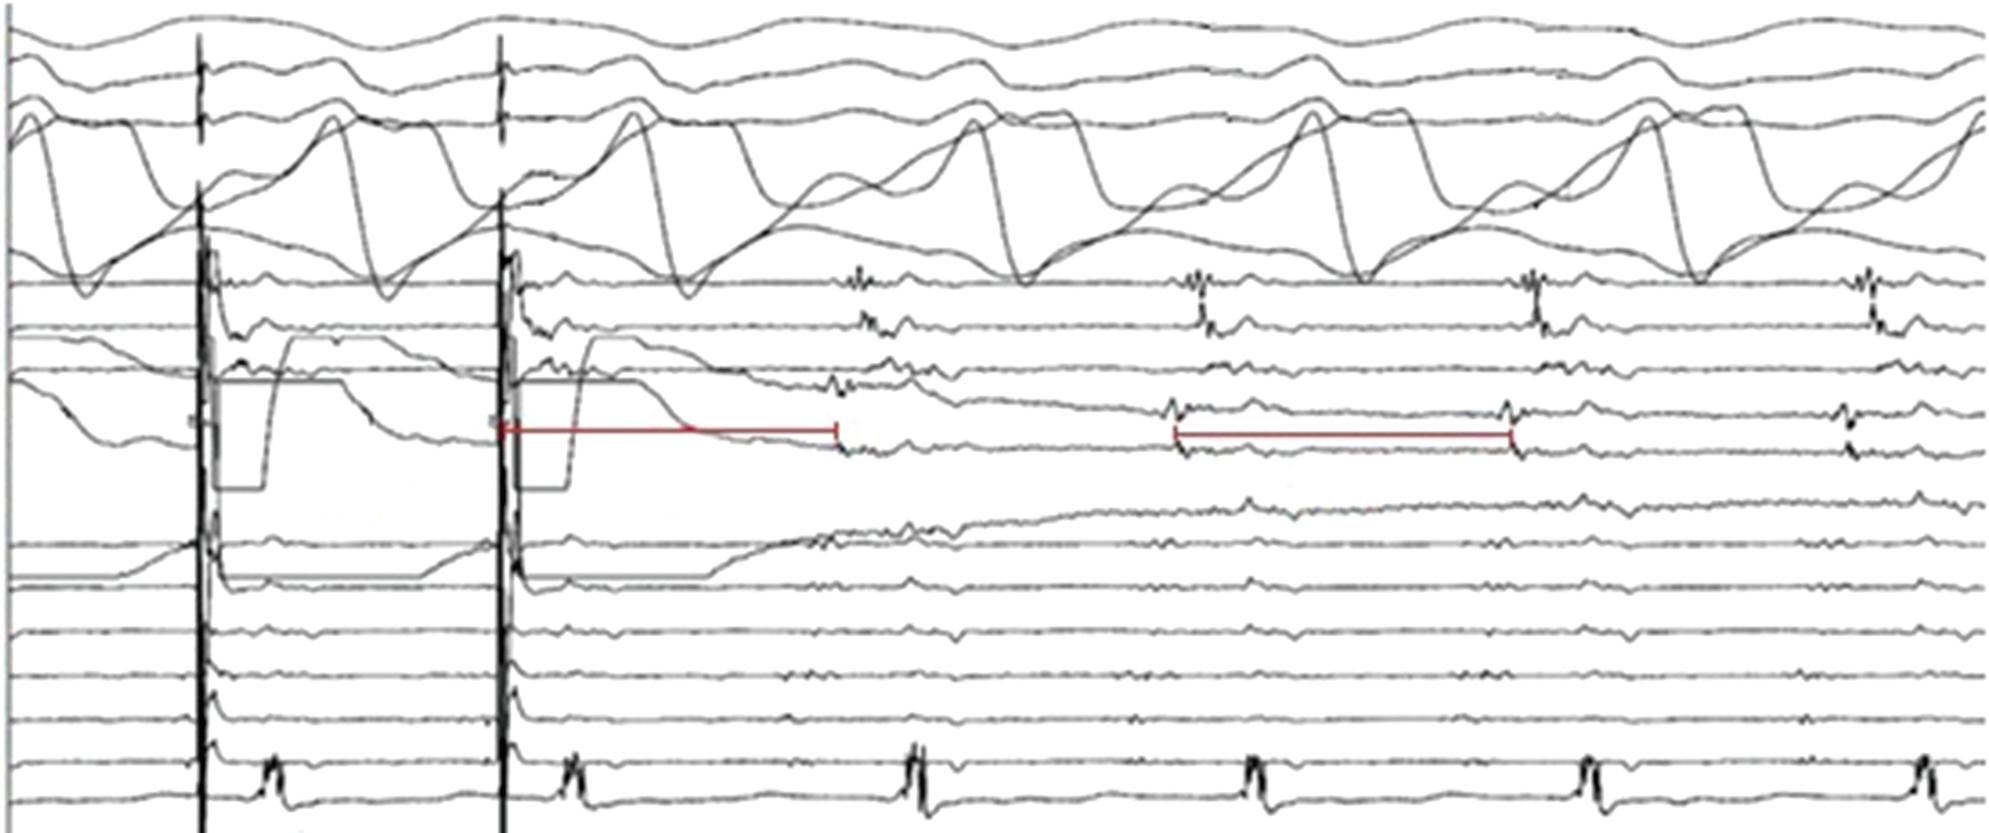

Figure 2: Gaps in Ablation Lesions After Pulmonary Vein Isolation

Examples of discontinuations of ablation-induced LGE lesions encircling the right (A) and left pulmonary veins (B), respectively, in a patient with AF recurrence after PVI. Left: 3D reconstruction of the LA with colour-coding based on image intensity ratios with thresholds for dense scar (red >1.32) and border zone (yellow 1.2–1.32), using ADAS 3D software). White arrows indicate local gaps. Pink lines indicate the plane of the left atrial LGE-MRI slices on the right; Middle: Overlay of the T1-weighted left atrial slices with the LGE colour-coding described above. White arrows indicate local gaps corresponding to the ones indicated in the 3D reconstructions on the left; Right: T1-weighted LGE-MRI slices without colour-coding. LA = left atrium; LAA = left atrial appendage; LGE = late gadolinium enhancement; LIPV = left inferior pulmonary vein; LSPV = left superior pulmonary vein; PV = pulmonary vein; PVI = pulmonary vein isolation; RPV = right pulmonary vein; RIPV = right inferior pulmonary vein; RSPV = right superior pulmonary vein.

Preprocedural LGE-MRI (1 day before PVI) A B Post-ablation LGE-MRI (3 months after PVI) Preprocedural LGE-MRI (1 day before PVI) Post-ablation LGE-MRI (3 months after PVI) LIPV LAA RIPV LSPV RSPV LIPV LAA Superior view Superior view Superior view Superior view RIPV LSPV RSPV LIPV LAA RIPV LSPV RSPV LIPV LAA RIPV LSPV RSPV

Figure 3: Agreement Between Electroanatomical Mapping and 3 Months Late Gadolinium Enhancement-MRI Regarding Gap Localisation

LGE-MRI-guided Repeat Ablation

Accumulating evidence indicates that LGE-MRI can detect and localise the gaps in ablation lesions with high accuracy (Figure 3).5–7 14 Overall, the accuracy and in particular the high sensitivity in the detection of gaps appears to be sufficient for LGE-MRI-guided repeat ablation – not only in the context of AF (Figure 4), but also with respect to post-ablation reentrant atrial arrhythmias (Figure 5).5 7 14

LPV entry

RPV entry

Activation maps of the LPVs and RPVs with conduction vectors (CARTO 3, coherent mapping with Pentaray catheter, Biosense Webster) indicating the entry site of the activation wave front (functional gaps) as detected during a repeat ablation procedure. Corresponding gaps detected by prior late gadolinium enhancement (LGE)-MRI (3 months post index ablation) are displayed in the small boxes. Colour-coding of the LGE maps (ADAS 3D software) is based on image intensity ratios with thresholds for dense scar (>1.32 red) and border zone (1.2–1.32 yellow), respectively. White arrows indicate localised functional gaps and LGE discontinuities, respectively. LPV = left pulmonary vein; RPV = right pulmonary vein.